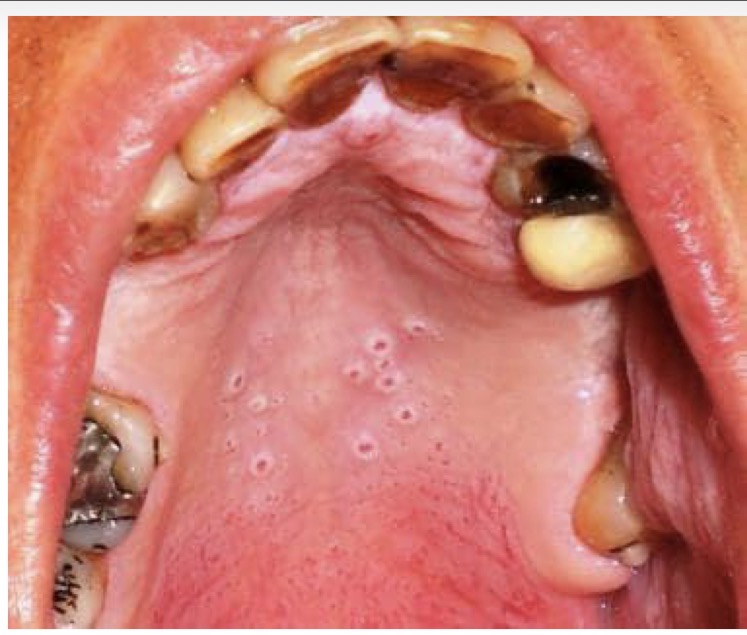

BN NAM, HÚT THUỐC LÂU NĂM

NỔI CÁC NỐT ĐỎ Ở VÒM MIỆNG

CHẨN ĐOÁN ?

VIÊM MIỆNG DO HÚT THUỐC LÁ